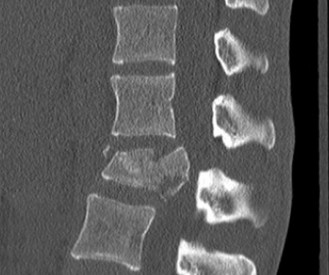

Initial trauma radiographs demonstrated a loss of anterior and middle column height at L1, with a focal kyphotic deformity. However, plain films are vastly insufficient for definitive surgical planning in thoracolumbar trauma. A high-resolution, fine-cut Computed Tomography (CT) scan of the entire spine was obtained. The CT images confirmed an L1 burst fracture with severe comminution of the vertebral body. Sagittal and axial reconstructions revealed 50% canal compromise secondary to a large retropulsed bone fragment originating from the posterosuperior aspect of the L1 vertebral body. Furthermore, the CT demonstrated 25 degrees of segmental kyphosis measured from the superior endplate of T12 to the inferior endplate of L1.

A critical finding on the axial CT slices was a vertical, split fracture propagating through the L1 lamina. This is a highly significant morphological feature. A lamina fracture in the setting of a burst fracture with retropulsion strongly correlates with a dural tear and potential entrapment of the cauda equina nerve roots. When the vertebral body bursts posteriorly, the pedicles are driven outward, and the lamina fractures as the spinal canal attempts to expand to accommodate the retropulsed bone. If the dura is lacerated, nerve roots can herniate through the dural defect and become incarcerated in the laminar fracture site.